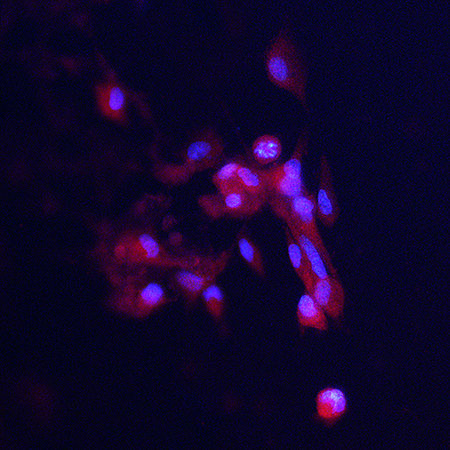

Neuromics 3D human blood-brain barrier model (cat. no. 3D45002) is the perfect tool for researchers studying the virus’ impact on the brain, as we continue to generate data demonstrating that our model truly mimics the properties of the BBB. Our model is developed to be highly reproducible, utilizing co-cultures of our human brain microvascular endothelial cells (cat. no. HEC02), human brain astrocytes (cat. no. HMP202), and human brain microvascular pericytes (cat. no. HMP104) layered in inserts to form the same tight junctions present in the BBB.

Earlier this week, we used IHC staining to check for ACE-2 expression in HBECs on the bottom of the inserts. Our results (see the image below) demonstrate that HBECs in our model express ACE-2, just as HBECs in the BBB in vivo.

While testing for ACE-2 expression, we received results (linked here) confirming the transendothelial electrical resistance (TEER) of our activated BBB model is in line with the BBB in vivo. Testing the TEER in all six inserts of our 12 well BBB model, we found that the TEER had a range of 165.66 Ω x cm2 to 270.93 Ω x cm2. With all readings exceeding the 150 Ω x cm2 minimum, our model further demonstrated its viability.

During the past few months, Neuromics has devoted much of our attention and expertise to helping how we are able during this pandemic. Much of this focus has been and continues to be spent on manufacturing and supplying virus transport media to those who need it. However, we are also excited to offer three new antibodies that are perfect for researching COVID-19. These SARS-CoV2 S-Protein ACE2 Binding Domain antibodies can help us better understand the virus and are perfect for vaccine research.

Image: Cells were transfected with the DNA encoding the S-protein segment in SARS-CoV2 binding domain protein which was inserted in the pCI-Neo-Mod expression vector. MO22195 produces clean and specific staining of transfected cells. The nuclei of transfected and untransfected cells are shown in blue with DAPI DNA stain.

The SARS-CoV2 virus’ spike or S-protein has been shown to interact with the ACE2 protein to bind and infect human cells. Our antibodies take advantage of this knowledge, allowing us to make antibodies to the ACE2 binding site of the SARS-CoV2 S-Protein. This allows research that can identify the presence of the SARS-CoV2 virus in western blots or immunofluorescence images (as seen in the images above and below).